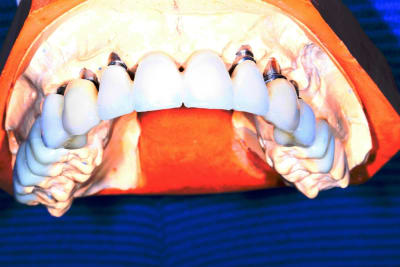

PXAV Je ne comprend pourquoi tu utilise des images 3D de piètres qualité dans tes présentations.

la suite.

Pxav , j aime bien l esprit des "facettes" vest sur les molaires .

Si c est pour aller chercher de la proprioception des chemins d entrees en post pour compenser le manque par le bridge implantaire , c est bien vu .

C est pas bete du tout .